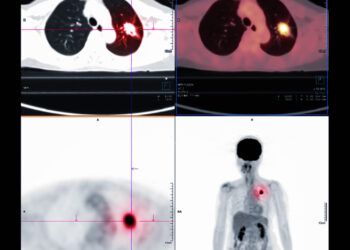

Skaityti daugiauDetailsKai sužinome apie onkologinę ligą, dažnai kyla daug klausimų: kokie tyrimai laukia, koks gydymo planas, kam reikalingi papildomi kraujo tyrimai....